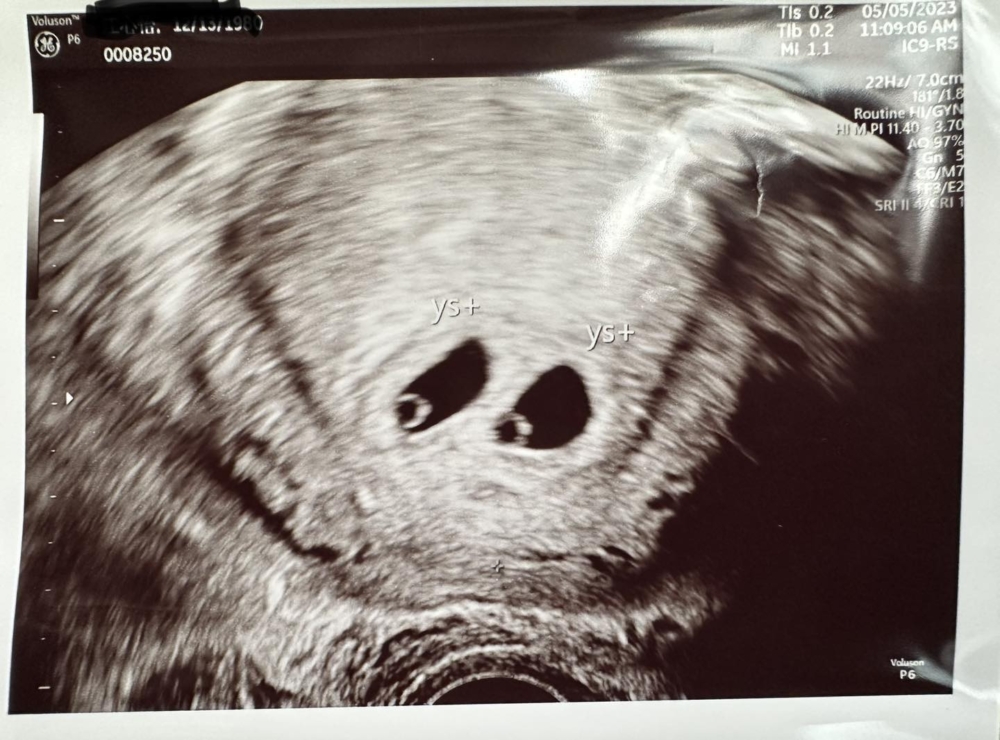

網紅作家「便當夫人」過去經常在社交平台紀錄為5名孩子準備的便當而走紅。去年一月,其4歲兒子晨翔不幸確診罹患罕見癌症DIPG(瀰漫性內生性腦幹膠質瘤),並於同年8月過世,一家人深受打擊,但也堅強地互相扶持,慢慢走出傷痛。今年母親節,便當夫人在社交平台上傳了一張超聲波相,宣布自己懷孕的消息,而且還是雙胞胎。